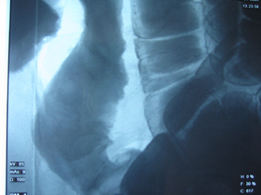

Στους ίδιους ασθενείς η εντερόκλυση μπορεί να αναδείξει ανάλογα ευρήματα με την ενδοσκοπική κάψουλα (εικόνες 36-43) ή να είναι φυσιολογική (εικόνες 44-48).

36  37

Εικόνες 36, 37. Ο ίδιος ασθενής με τις εικόνες 15, 16. Εικόνα πλακόστρωτου με στένωση και παρουσία        βαθιάς εξέλκωσης του βλεννογόνου